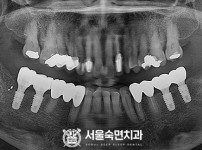

상악동거상술, 뼈이식 / 숙면임플란트 13개 - 오스템임플란트 (이*웅님)

해당 게시물은 의료법 제56조에 의거하여 로그인 후 열람이 가능합니다.

구분 임플란트